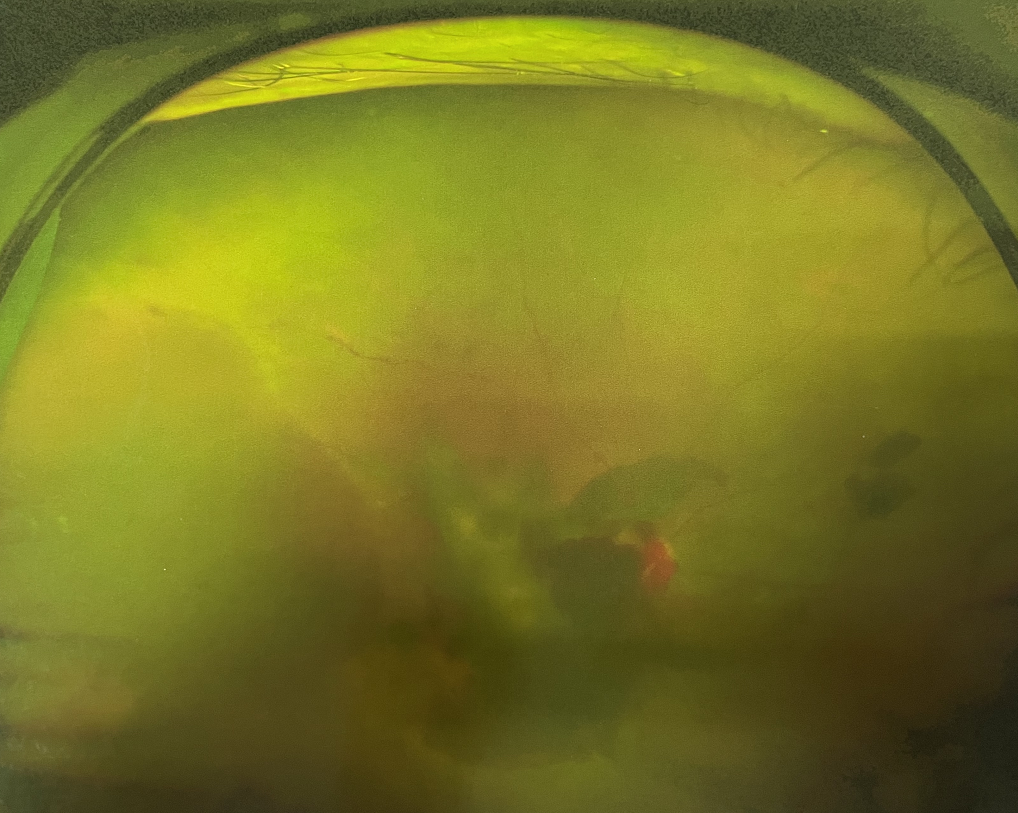

眼底出血多指玻璃體內(nèi),眼睛更深處的視網(wǎng)膜出血。通常情況下,肉眼難以發(fā)現(xiàn)眼底出血,而且發(fā)病初期眼睛也無(wú)明顯癥狀,只有借助專業(yè)的眼底檢查儀器才能觀察到異樣。那么眼底出血嚴(yán)重嗎?

眼底出血嚴(yán)重嗎?對(duì)于已出現(xiàn)黃斑水腫、視網(wǎng)膜新生血管的患者,根據(jù)眼底血管造影、oct等檢查結(jié)果,給予玻璃體腔注射抗VEGF藥物及激光治療,可以減輕黃斑水腫,使視網(wǎng)膜新生血管消退,以免進(jìn)一步發(fā)生玻璃體出血、視網(wǎng)膜脫離等嚴(yán)重并發(fā)癥的出現(xiàn)。對(duì)于玻璃體出血者,傳統(tǒng)認(rèn)為玻璃體出血3-6個(gè)月不吸收再進(jìn)行手術(shù)干預(yù),但近年來因?yàn)轱@微手術(shù)設(shè)備及玻璃體切割技術(shù)已非常成熟,故對(duì)于1個(gè)月不吸收的玻璃體出血者就可以考慮手術(shù),即手術(shù)時(shí)機(jī)應(yīng)該具體情況具體分析,因人而異。